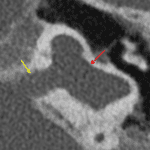

Age: 15 months

Sex: Female

Indication: Left greater than right sensorineural hearing loss

Common cavity malformation